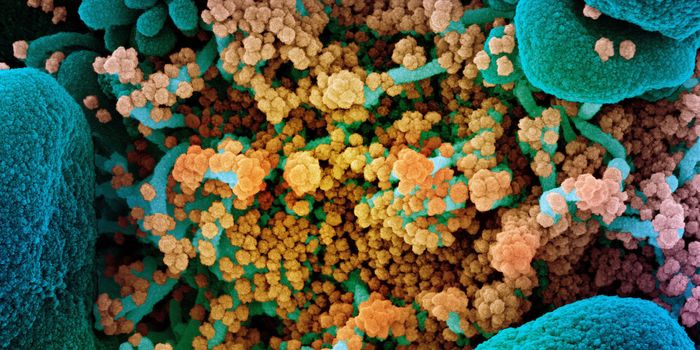

JUL 05, 2020Cell & Molecular BiologyThe pandemic virus SARS-CoV-2 enters the body through the respiratory system to cause the illness COVID-19. But we know ...

MAR 18, 2020MicrobiologySARS-CoV-2 is a coronavirus that causes an illness called COVID-19. There are now well over 210,000 confirmed cases worl ...

APR 06, 2020Genetics & GenomicsSARS-CoV-2 is the name for the pandemic coronavirus that causes the illness COVID-19, which affects people in extremely ...